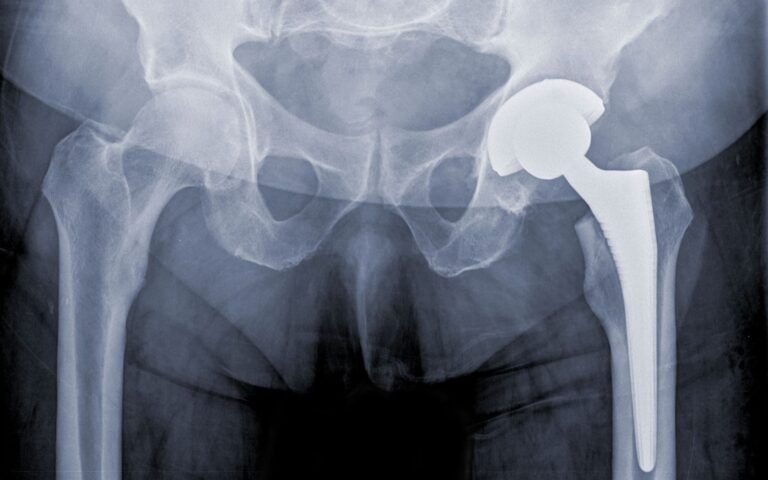

Total Hip Replacement Surgery

Effective treatment to restore hip joint function with long-lasting results.